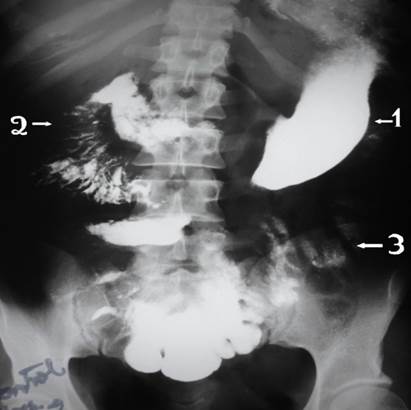

Liquido inflamatorio libre en cavidad, isquemia intestinal masiva desde el duodeno a colon transverso en un paciente (Imagen 1), desde una porción de aproximadamente 15 cms del ángulo de treitz a colon transverso en el segundo paciente (Imagen 2), en el tercero encontramos gangrena intestinal desde 10 cms del ángulo de treinta hasta la mitad del colon transverso derecho (Imagen 3).

Ilustración 1 Isquemia intestinal masiva

Fuente: Hospital de Especialidades Guayaquil “Doctor Abel Gilbert Pontón”.

Autor: Dr. Fernando Moncayo A.

Se verifico el tránsito corto mediante estudio de tránsito baritado intestinal (Imagen 7,8.9)

Ilustración 7 Tránsito gastro-intestinal postquirúrgico; se verifica contraste que pasa desde duodeno al colon directamente